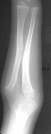

A 4 year and 6 month old male sustained a fall onto an outstretched left arm. He presented to the emergency room with forearm deformity and acute pain(image 1). It was treated with closed reduction and casting (image 2&3). The patient was brought back for another evaluation 10 months after the initial injury(image 4). An x-ray at that time was repeated. On physical examination, he has a prominence over the left radial head. There is full flexion and extension. He has full pronation but lacks 30 degrees of full supination. He is neurovascularly intact(image 5).

At 10 months following the injury, you can inform the parents that many children may still have this radial head reduced and develop almost normal range of motion.